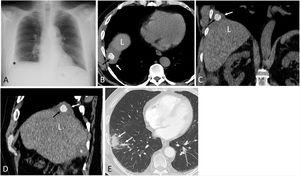

A 67-year-old patient presented to our hospital with cough and chest pain four months after undergoing a scheduled laparoscopic cholecystectomy for cholelithiasis. A chest radiograph showed a new-onset small right basal opacity and an ipsilateral costophrenic angle obliteration (Fig. 1A). Due to persistent chest pain despite analgesic treatment, a thoracic computed tomography (CT) was performed, which demonstrated a small right pleural effusion, a calcified polyhedral image within the ipsilateral pleural cavity, and inflammatory changes in the lateral basal segment of the right lower lobe (Fig. 1B–E). These findings were consistent with pleurolithiasis of biliary origin (PLBO) probably secondary to inadvertent intraperitoneal spillage of biliary content during laparoscopic surgery with posterior transdiaphragmatic migration. The patient underwent thoracoscopic removal of the pleural gallstone, lysis of adhesions, and partial resection of the lateral basal segment of the right lower lobe, with disappearance of his symptoms. No apparent diaphragmatic defect was demonstrated during surgery.

(A) Posteroanterior chest radiograph shows a small right basal opacity (asterisk). (B)–(D) Axial (B), coronal (C), and sagittal (D) thoracic CT images (mediastinal window) show a polygonal calcified lesion in the right pleural space (black arrow). Note the small pleural effusion (white arrow). “L” represents the liver. (E) Axial thoracic CT image (lung window) shows inflammatory changes in the right lower lobe (arrows).